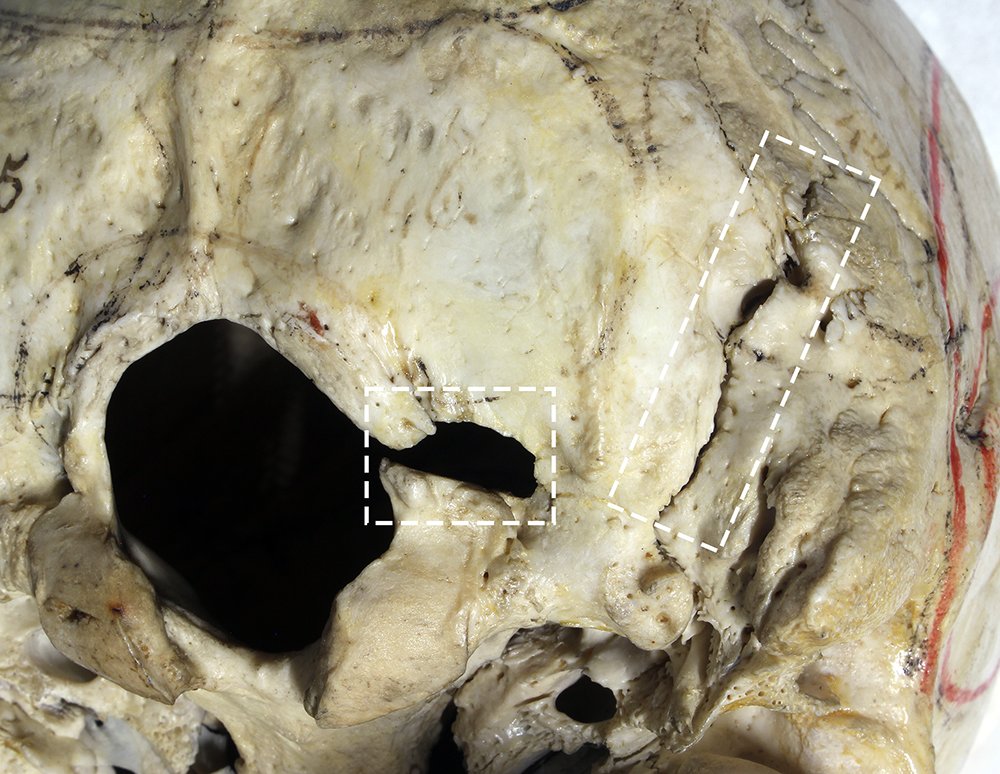

Cranial base fractures are typically classified by region: anterior (frontobasal) fractures often result from direct frontal impact, central skull base fractures commonly extend from frontobasal fractures, and posterior skull base fractures usually occur due to direct occipital impact and may extend into the petrous part of the temporal bone (Baugnon and Hudgins 2014). Only posterior skull base fractures, affecting three individuals, were observed in the Karlau Prison population sample. One of these cases comprised two perimortem fractures in an individual (No. 137) who died by judicial hanging. These fractures included a unilateral (right) occipitomastoid diastasis and a hole fracture (approximately 8 × 6 mm in size) posterior to the right occipital condyle and extending to the lateral margin of the foramen magnum (Fig. 2). The fractures are likely directly related to the cause of death rather than damage caused during the anatomical dissection. Occipitomastoid diastatic fractures have been reported in other cases of judicial hanging-related skeletal trauma (Campanacho and Garcia 2021; Waldron 1996; Wood-Jones 1913).

Figure 2. Perimortem fractures observed in the posterior cranial base of a 26.4-year-old (No. 137), who died by judicial hanging. A hole fracture is noted immediately posterior to the right occipital condyle, as well as an occipitomastoid diastasis on the right side of the skull base. Photo: Jonny Geber.

The additional two individuals with injuries to the cranial base displayed antemortem fractures (Fig. 3). These included a linear fracture in the process of healing on the left aspect of the occipital bone of a 44.0-year-old individual (No. 78), where a fracture line extended onto the temporoparietal suture where it is diastatic. The second skull belonged to a 57.0-year-old individual (No. 124), which displayed a healed linear fracture running diagonally across the left aspect from the jugular junction to the external protuberance. Linear fractures affecting the neurocranium generally originate distant from the in-bending impact area of the bone and radiate both toward and away from where the impact occurred (Galloway 1999). The linear fractures in these individuals were both confined to the occipital bone, and both on the same side, likely as a consequence of being struck from the front or left while moving the face away from an aggressor.